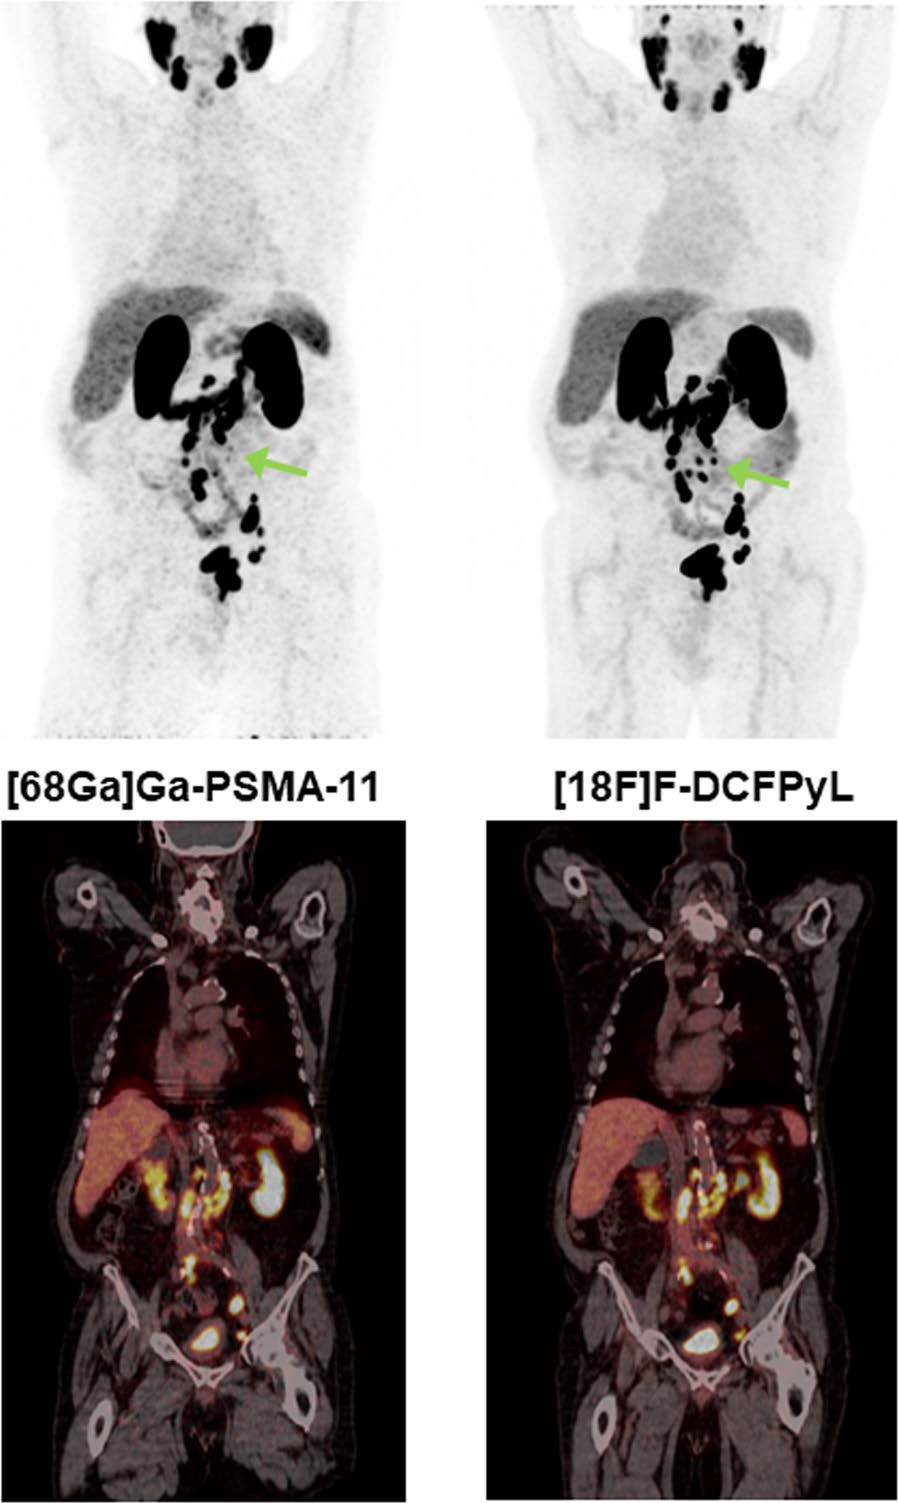

Prostate-specific membrane antigen (PSMA) PET imaging could improve the length and quality of life for patients with recurrent prostate cancer, according to a study published October 23 in JAMA Network Open.

Although studies have shown that PSMA-PET is highly effective for detecting prostate cancer, the long-term consequences of widely implementing the technique in patients with recurrent disease are unknown, the authors explained.

The model simulated three alternative strategies that patients may encounter: immediate PSMA-PET without conventional imaging, PSMA-PET imaging as a reflex test if conventional imaging findings are negative or equivocal, and conventional imaging alone.